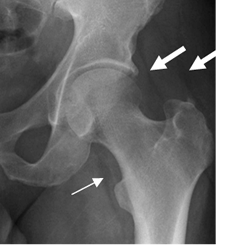

Existen cojinetes grasos que rodean los músculos glúteos, iliopsoas y obturador, que pueden ser identificados. Aunque son inconstantes, su desplazamiento o desaparición al hacer un estudio comparativo, sugieren la presencia de derrame articular. (5). (Fig 15).

Fig 15. Cojinetes grasos.

Rx AP. Cojinetes normales del iliopsoas (Flecha delgada) y glúteos (Flecha gruesa).